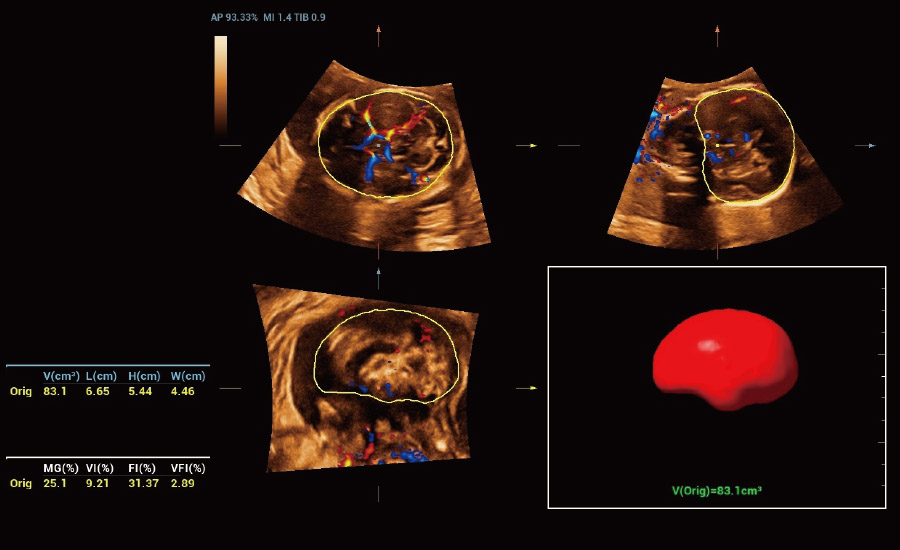

UMA (Ultra-Micro Angiography)

The innovative technology breaks the bottlenecks of traditional Doppler imaging. With ultra-high spatial resolution and flow sensitivity, it allows detecting super-subtle and super-slow flow perfusions, thereby extending the clinical application of qualitative and quantitative ultrasound evaluation in fetal brain, kidney, placenta, endometrium, ovary, etc.

3D UMA - perifollicular blood flow

Combining advanced algorithms and domain-specific knowledge, the innovative Smart Scene solution enables auto identification of tissue characteristics and provides organ-specific diagnosis with full-stack intelligence. Based on auto scenario identification, the solution not only realizes smart 2D scanning with auto settings and measurements, but also delivers 3D full-stack intelligence in every step from volume imaging optimization to the difficult 2D plane acquisition, and quantification throughout whole procedure. It helps a lot in reducing the dependency on clinical skills, while increasing diagnostic accuracy, confidence and efficiency.